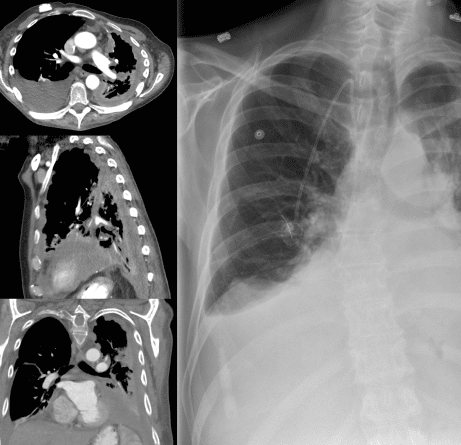

El mesotelioma es un cáncer agresivo que se desarrolla en la capa de tejido que recubre la mayoría de sus órganos internos. El tipo de mesotelioma varía dependiendo de dónde se haya detectado el cáncer.

- Mesotelioma pleural (tejido pulmonar)

Quienes han inhalado asbesto también pueden padecer asbestosis, que es una cicatrización del tejido pulmonar que causa problemas respiratorios. Otro problema son las placas pleurales, causadas por cicatrices en las zonas que rodean los pulmones y en la parte superior de la caja torácica. Asimismo, inhalar fibras de este material puede provocar cáncer de pulmón.